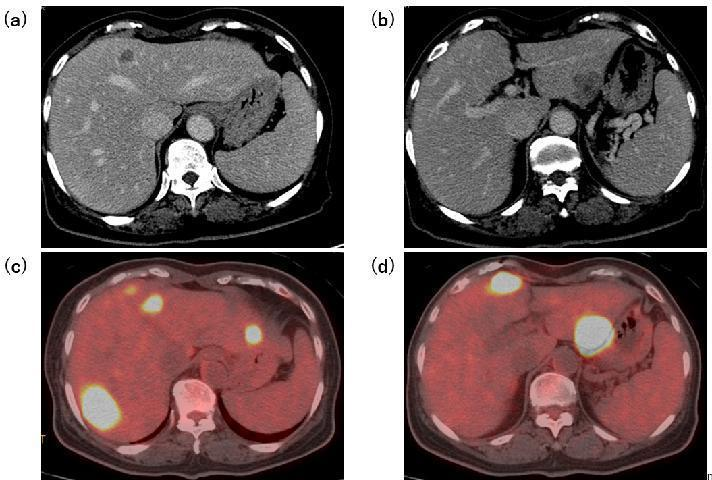

增强CT:提示多发性肝、淋巴结转移(图1b,图2a、b)。

全身FDG-PET:原发部位胃以及7个肝转移灶代谢增高(图1c,图2c、d)。

图2:初诊时CT及FDG-PET(a、b,增强CT;c、d,FDG-PET)